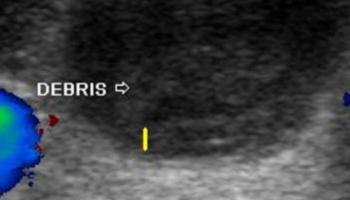

- obecności zmian patologicznych - np. torbiele, zmiany guzkowe (ich lokalizacja, charakter unaczynienia, ewentualnie ocena naciekania otaczających struktur)

Część zdjęć pochodzi ze strony www.ultrasound-images.com